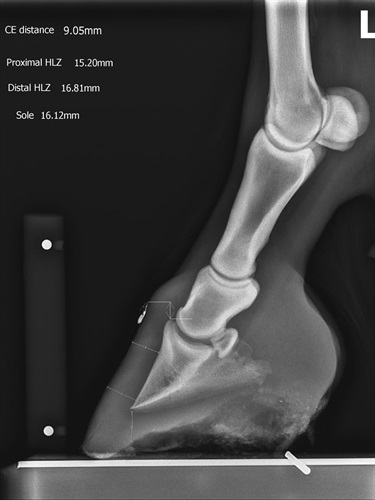

Dr Tanya Meares is a qualified veterinarian who regularly travels across Western Victoria sustaining a working relationship with many beloved horses. Tanya has a portable x-ray device that is ideal to diagnose Laminitis and other hoof conditions.

Grampians Equine Hoof Care has the expertise and will work with you to develop a long-term treatment and management plan for your loved horse/s.